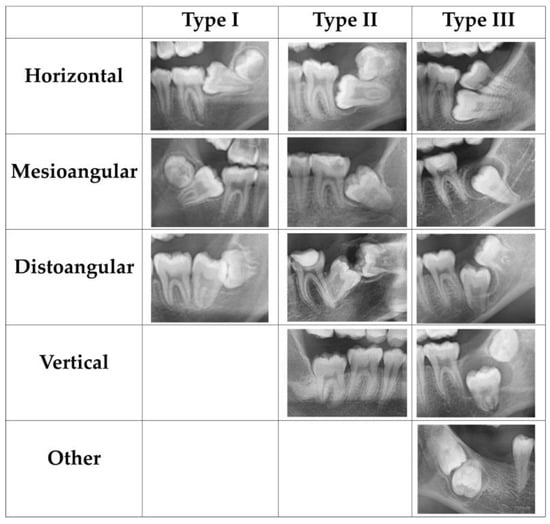

| Item/Impaction Type | Type I | Type II | Type III | Total | p-Value |

|---|---|---|---|---|---|

| Angulation (n) | <0.001 ** | ||||

| Horizontal | 7 | 6 | 6 | 19 | |

| Mesioangular | 55 | 30 | 17 | 102 | |

| Vertical | 0 | 1 | 5 | 6 | |

| Distoangular | 1 | 1 | 5 | 7 | |

| Other | 0 | 0 | 3 | 3 | |

- The majority of impacted MM2 with Type I or Type II were caused by insufficient space, while impacted MM2 with Type III were attributed to a variety of causes, including insufficient space, ectopic path, and cysts.

- The majority of impacted MM2 in Type I and Type II were mesioangular, and Type III presented various angulations.